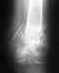

В марте сломал ключицу (многооскольчатый перелом со смещением). Сделали операцию и поставили пластину. После чего наблюдался в местном травмпункте, где через 3 недели сделали прямой снимок и сказали, что всё ОК, но на снимке пластина перекрывала ключицу. Второго снимка в нужной проекции сделано не было. Физиотерапию тоже не назначали. Гипс не накладывали. В июле почувтвовал боли и пощёлкивания в месте перелома. Вскрыли - обнаружилось несращение, сместилась пластина и вырваны шурупы. Провели вторую операция - опять поставили пластину. Наложили гипсовую повяхку, которая фиксирует локоть - мог шевелить только кистью. Опять после выписки наблюдался в местной травме. Там же вновь сделали рентген через 3 недели в прямой проекции, сняли и гипс и сказали, что всё в порядке. В середине сентября снова почувствовал боли и пощёлкивания. 22.09.09 сделали третью операцию, поставили новую пластину и аутотрансплантант из бедра подвздошной кости. В больнице из процедур прошёл: 5 раз магнитотерапию, 2 раза барокамеру, 5 руз УФО крови. Наложили такую же гипсовую повязку. После выписки в травму уже не пошёл и наблюдаюсь у перировавшего хирурга. Дополнительно ходил на магнито-лазеротерапию: пока 9 сеансов с 13.10 по 23.10. Параллельно пил Кальций Д3 компливит, мумие, витамины Супрадин. 23.10 сделали рентген - снимок прикрепил. Врач сказал, что нужно ещё отходить минимум в гипсе 2 недели, желательно 3. Врачу доверяю целиком и полностью, но всё таки хотелось бы посоветоваться. В связи с тем, что 27.11 нужно будет при любых обстоятельствах выехать из страны и даже если не срастётся придутся снять гипс, возникли вопросы: 1) Как ускорить сращение? 2) Имеет ли смысл предложить врачу ввести в место перелома Коллапан? 3) Какие физиопроцедуры можно ещё проделать, учитывая, что у меня стоит металлическая пластина: ударно-волновая терапия, Интерференционные токи или что-нибудь ещё? 4) Какие препараты пропить?